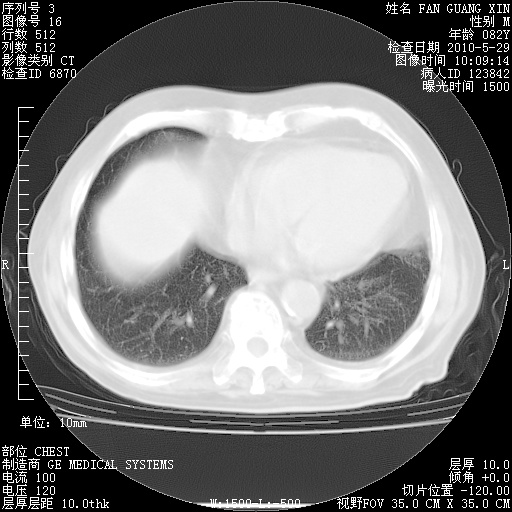

再治疗10天后的肺部CT

从白细胞总数和中性比例看好像合并感染。肺部纹理好像比上次多,支气管炎?其他感染?

阅读此次胸部CT,肺间质渗出性改变较入院时有吸收。目前从体温、白细胞、中性分叶明显增高,肯定存在细菌感染(发生医院感染哦,若无消化道及泌尿系统等感染的依据,肺部感染可能大)。若你院头孢哌酮舒巴坦钠耐药率较高,同意你的方案,若48小时体温仍高,可考虑使用碳青霉稀类抗菌药物,同时可予超声雾化、注意滴数时加大液体量。白蛋白33.30g/L较低哦,需加强营养等支持治疗。